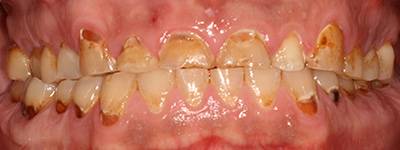

6. Eset

Nagymértékű fogkopás, erózió, csikorgatás a teljes rágóapparátust túlterhelve okoz reménytelennek tűnő helyzeteket.

Ebben az esetben implantátumok , koronák és hidak segítségével változtattunk a páciens fogainak érintkezésén. 6 hónapig ideiglenes hidakkal teszteltük a megváltoztatott harapási pozíciót. Ezután készültek el a végleges fix pótlások.